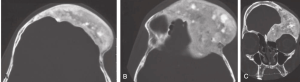

- CT Imaging: Expansile remodeling of bone, ground-glass appearance.

- MRI: For cranial nerve compression.